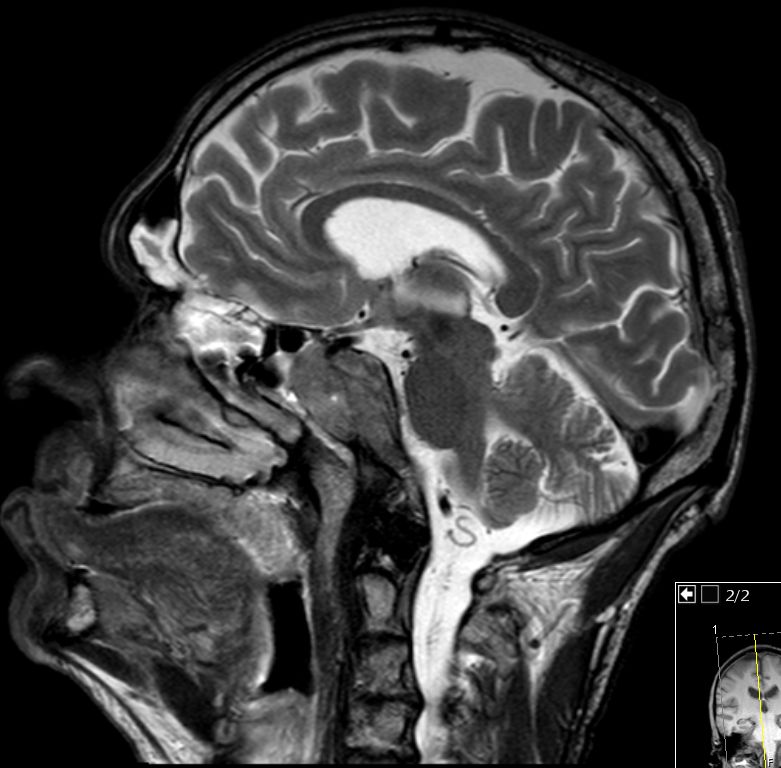

55-jähriger Mann, der vor 6 Monaten wegen eines Oropharynxkarzinoms links pT3 pN0 M0, L1, V0, Pn1 radikal operiert wurde und eine postoperative Radiochemotherapie mit Cisplatin erhielt. Jetzt Schädelbasis-Metastase im Bereich des Sinus cavernosus. Klinisch Hirnnervenausfälle links N. abducens, rechts N. opticus, - trochlearis, - trigeminus 1. Ast, unsicheres Gangbild, Störung des Schluckaktes. | ||